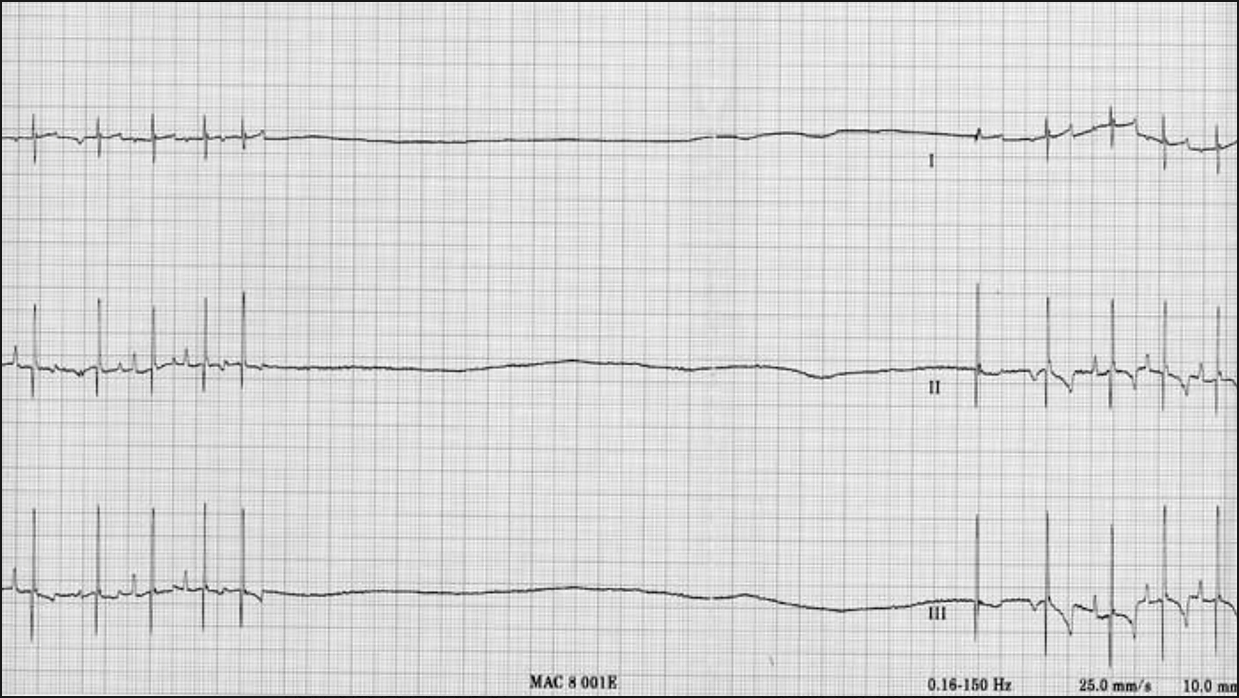

Asystole:

This is where there is a lack of any contraction in the ventricles and subsequently there is a period of no electrical activity (flat line) on the ECG.

It normally occurs from degeneration from ventricular fibrillation when the myocardium eventually runs out of energy and stops fibrillating altogether. However this is not the case in this ECG.